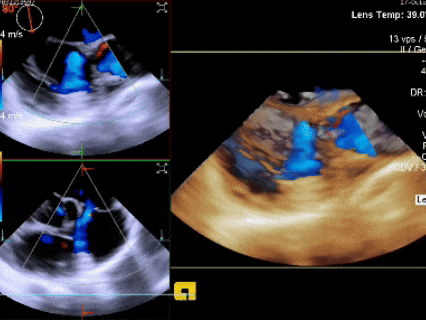

三维下可见房间隔缺损

三维下看到导丝成功过隔

鞘管配合加硬导丝顺利通过缺损,可见双轨征